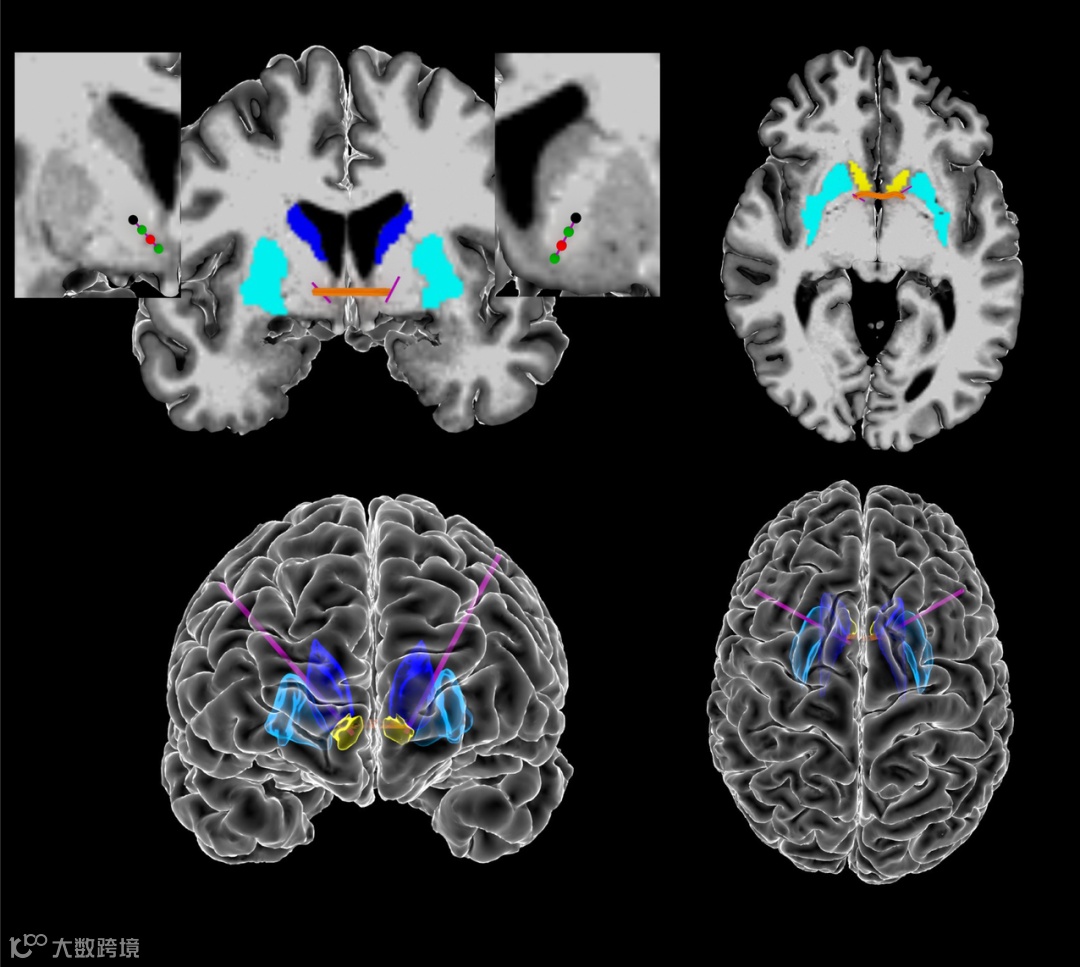

图 | 颅内电生理数据的采集(来源:Nature)

结果发现,与以往的经验不同,强迫症的大脑信号不仅仅来自于大脑腹侧内囊/腹侧纹状体 ,也来自于大脑皮质-纹状体-丘脑-皮质环路。除了脑电波信号,研究人员还收集了一套强迫症患者行为的生物标志物,包括面部表情和身体运动。通过人工智能,他们发现这些行为和特征与大脑内部信号变化密切相关。

图 | 大脑深部刺激的作用示意(来源:Nature)